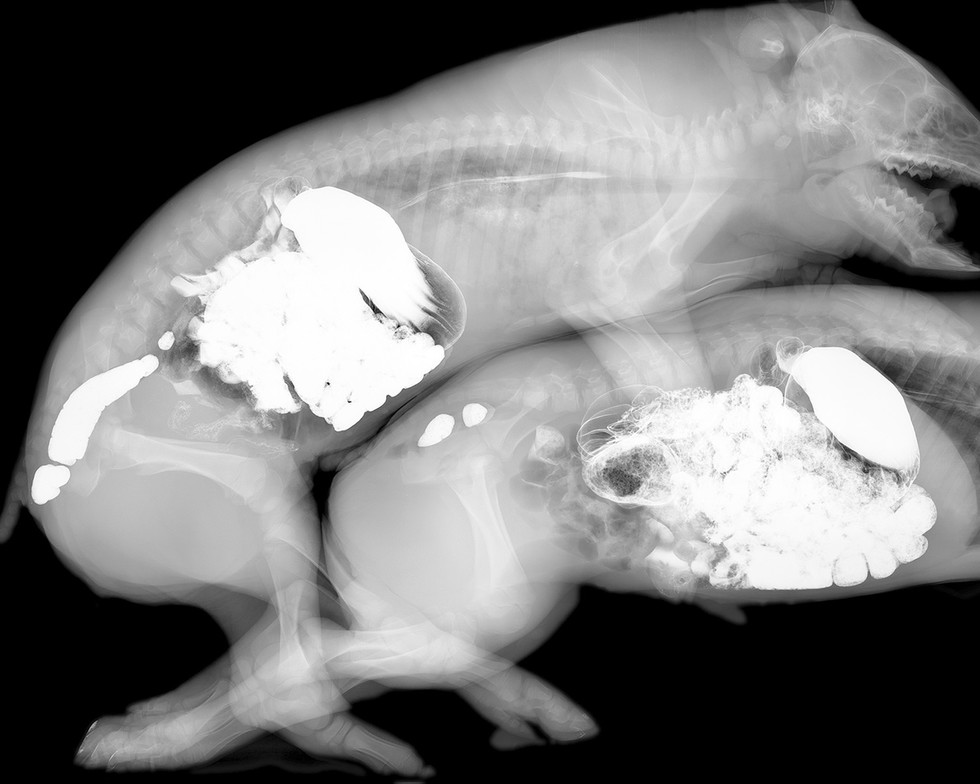

Delvoye also extended the project beyond human subjects. The series came to include X‑rays of animals such as pigs and snakes, along with scans of organic materials including intestines and sliced meats. Other panels move further toward abstraction, using swirling patterns of spinal columns or rows of teeth layered against backgrounds of deep red glass. The imagery oscillates between anatomical diagram and ornamental pattern, echoing the decorative rhythms of traditional stained-glass windows while simultaneously confronting viewers with the internal structures of the body.

For the stained glass window works, Delvoye used X‑ray images taken during intimate encounters between two friends. The skeletal images produced by the radiographs were incorporated directly into stained-glass compositions and placed within Gothic-style window frames. From a distance the windows appear abstract, their luminous shapes resembling decorative patterns of light and color. Only when viewed closely do the anatomical elements emerge: skulls, teeth, spinal columns, and ribs forming intricate visual arrangements. In some panels the figures are clearly interacting, even kissing.

The imagery itself consists primarily of thousands of individual radiographic frames depicting skeletal structures, spinal columns, skulls, teeth, lungs, and various bodily gestures. In place of saints or biblical scenes, Delvoye created panels so that they would depict skeletal figures embracing, kissing, and interacting within the architectural frameworks of typical Gothic church windows. Yet the images reveal very little of the emotional dimension of human intimacy. Instead, the bodies appear as mechanical structures, bones and joints moving through space, suggesting that radiography reduces the human body to a kind of biological machine.

Inside the chapels the luminous panels produce a striking visual effect. Radiographic images of hips, skulls, ribs, and spines intertwine to form compositions that glow like traditional stained glass. Because X‑rays transmit light in much the same way as colored glass, the panels illuminate easily, producing a glittering yet macabre atmosphere. The resulting environment is both beautiful and unsettling.